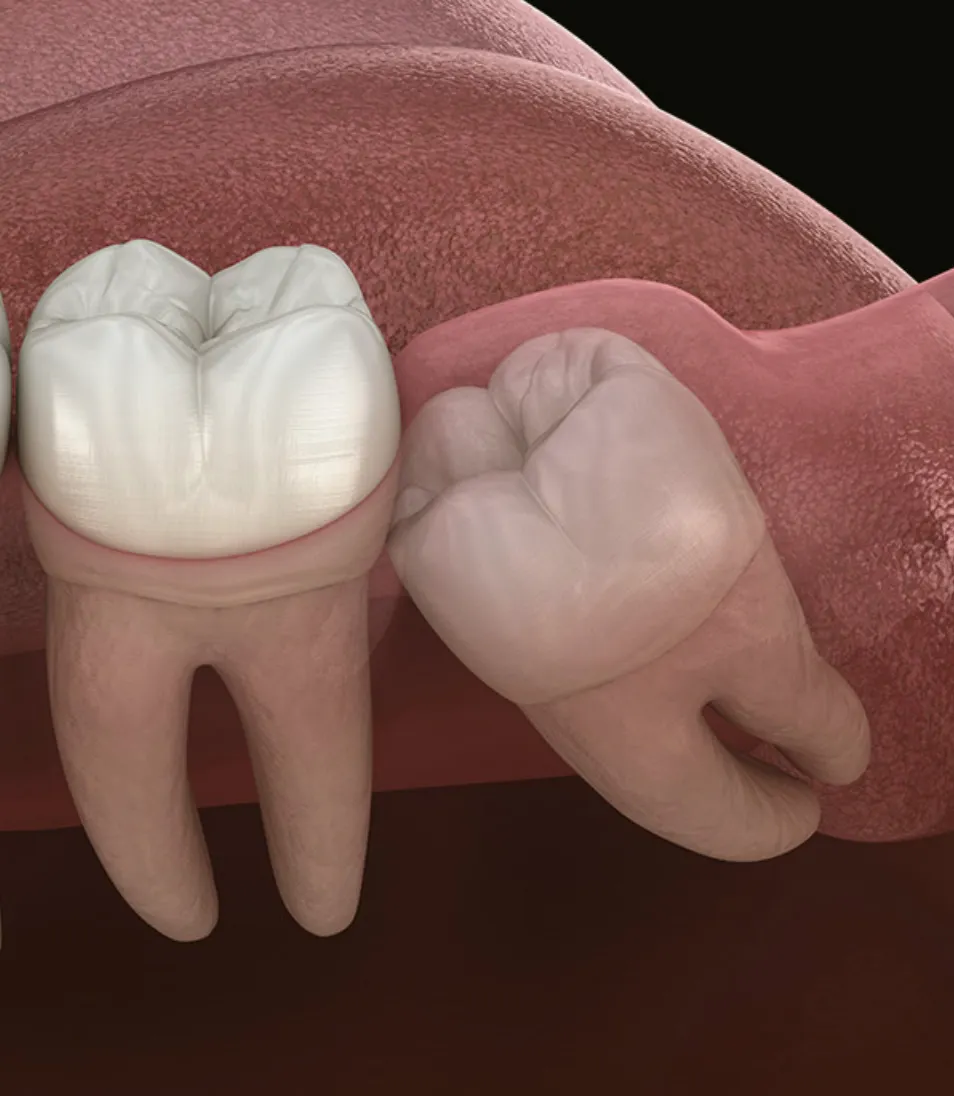

사랑니가 비스듬하게 누워있는 경우, 구강악안면외과 전문분야인 외과적 수술을 통해 사랑니를 발치합니다.

매복 위치에 따른 전문적인 추가 수술

사랑니는 매복위치에 따라 수술 난이도가 달라집니다. 보통은 잇몸수술을 동반하게 되고, 치아 분할이나, 뼈 삭제 과정 등이 필요하게 될 수 있습니다.

매복사랑니는 매복된 위치에 따라 난이도가 다릅니다. 보통 잇몸 수술을 동반해서 치아 분할, 골 삭제가 이뤄지므로 많이 불편할 수 있는 과정입니다. 최소절개, 최소삭제를 원칙으로 발치를 진행하여 수술 기간과 후유증을 최소화합니다.